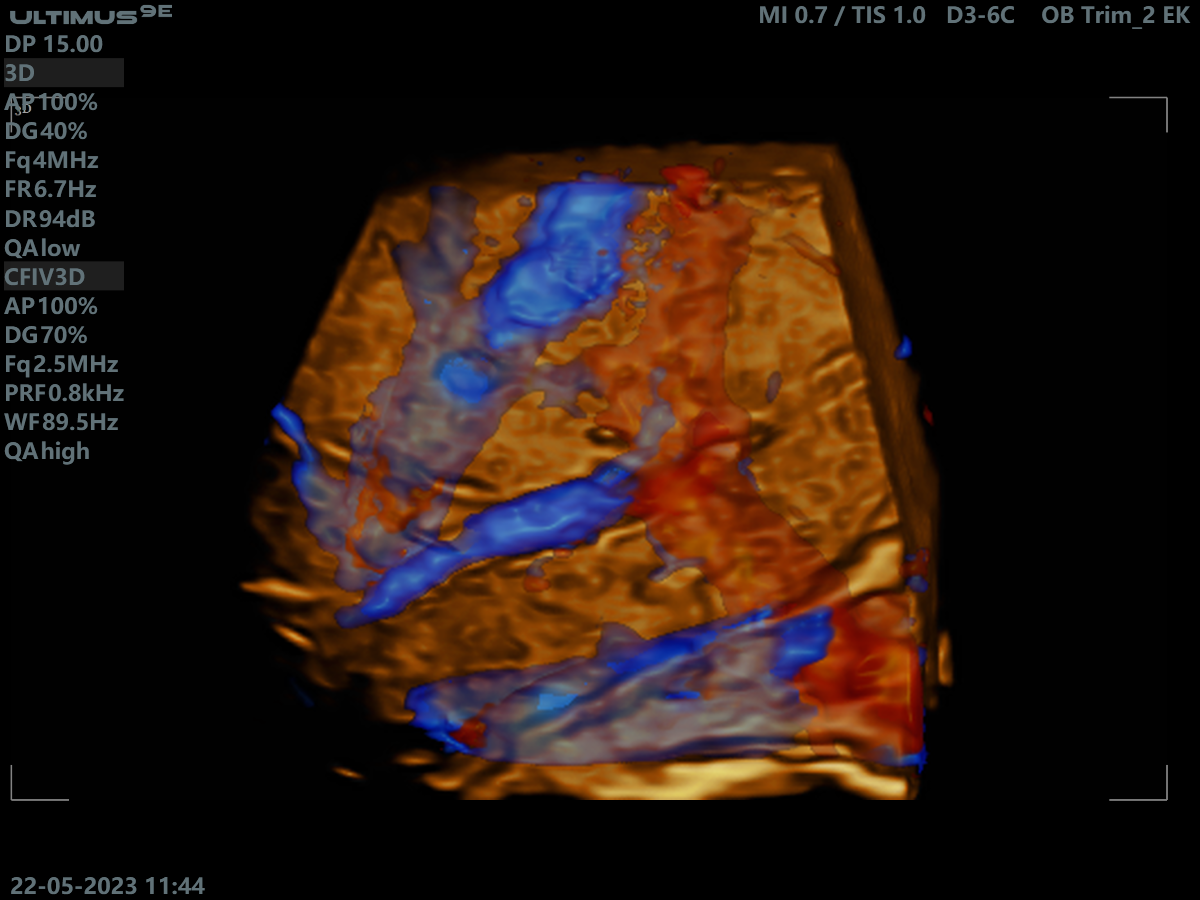

Клінічні зображення, що демонструють якість діагностики та можливості обладнання

Клінічне зображення 2

Клінічне зображення 3